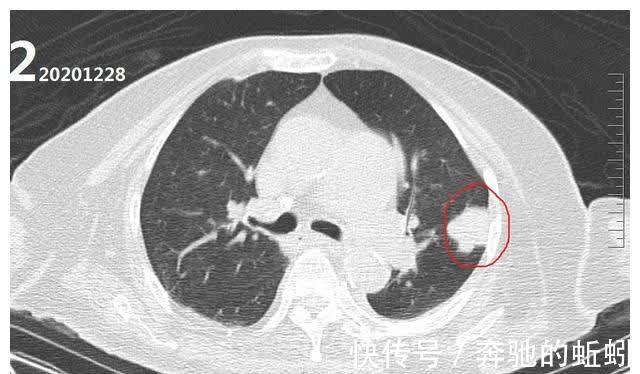

动脉瘤血管内栓塞术后,因蛛网膜下腔出血量较大,患者一直处于昏迷状态,20201228日复查头颅CT及胸部CT时,胸部CT情况如(图2)左肺病灶未见明显增大。因患者当时身体状态不佳,对左肺病灶仍未进行针对性诊治。